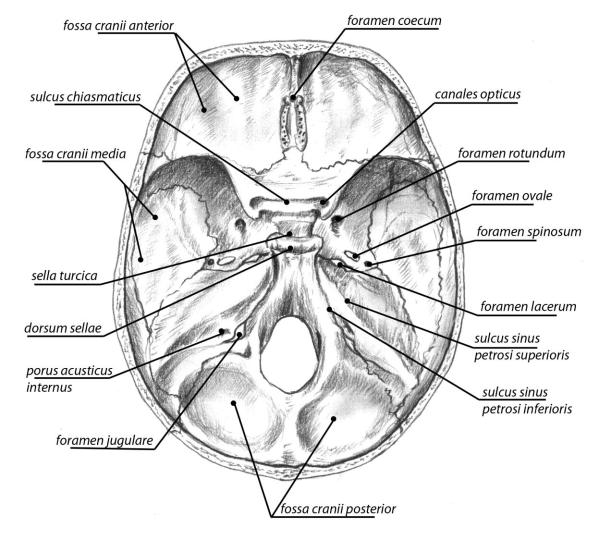

Анатомические детали: Фотографии топографии черепа с нижнего вида

Раздел: Альбом идей